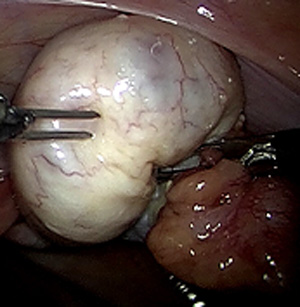

Laparoskopische Myomenukleation

Bei "Myomen" handelt des sich um gutartige "Muskelknoten", die am häufigsten in oder an der Gebärmutter vorkommen. Anzahl, Größe und die genaue Lage können dabei stark variieren Myome treten häufig ohne Symptome auf, dass heißt, sie verursachen nicht unbedingt Beschwerden. Es besteht dann keine zwingende Notwendigkeit zur Operation. Typische, durch Myome verursachte Beschwerden sind starke, häufig auch schmerzhafte Menstruationsblutungen. Mit zunehmender Anzahl und Größe der Myome kann sich die Gebärmutter insgesamt deutlich ausdehnen, so dass ein "Druck" oder Schmerz im Unterbauch entsteht. Abhängig von Lage, Größe und Anzahl der Myome können diese unter Umständen die Entstehung einer Schwangerschaft verhindern oder ein Grund für eine Fehlgeburt sein. Myome, die deutlich an Größe zunehmen, oder die Symptome verursachen, sollten operiert werden. Verschiedene nicht operative Behandlungsmethoden zeigen häufig nicht den gewünschten Erfolg oder sind bei manchen Patientinnen nicht anwendbar. In diesen Fällen ist eine Operation notwendig. Im Rahmen der Voruntersuchung beraten wir Sie bezüglich der Frage ob und ggf. auf welchem Wege operiert werden sollte. Auch eine Beratung im Sinne einer "zweiten Meinung", also ohne den Wunsch einer Operation, ist nach terminlicher Absprache möglich.

Myome, die sich in der Gebärmutterwand (intramural) oder auf der Außenseite (subserös) des Uterus befinden, können in aller Regel per Bauchspiegelung entfernt werden, dabei wird ein sogenanntes Laparoskop durch den Bauchnabel geführt. Verbunden mit einem Kamerasystem ermöglicht es dem Operateur im Bauch "sehen" zu können. Mit zwei bis drei zusätzlichen Instrumenten können die Myome mittels minimal-invasiver Operationstechnik aus der Gebärmutter "herausgeschält" und entfernt werden. Die Gebärmutter wird dann wieder vernäht. Vor einer eventuell geplanten Schwangerschaft wird empfohlen, einen Zeitraum von drei bis sechs Monaten abzuwarten. Die Technik der Laparoskopie ermöglicht es, die mit einem Bauchschnitt verbundenen Schmerzen zu vermeiden - dennoch kann es unter Umständen sinnvoll sein, sehr große oder ungünstig gelegene Myome, durch einen Bauchschnitt zu entfernen